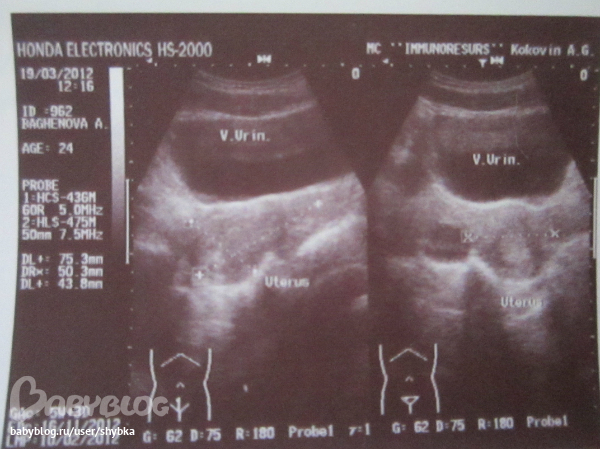

21 дпп узи

21 дпп узи 118 фото